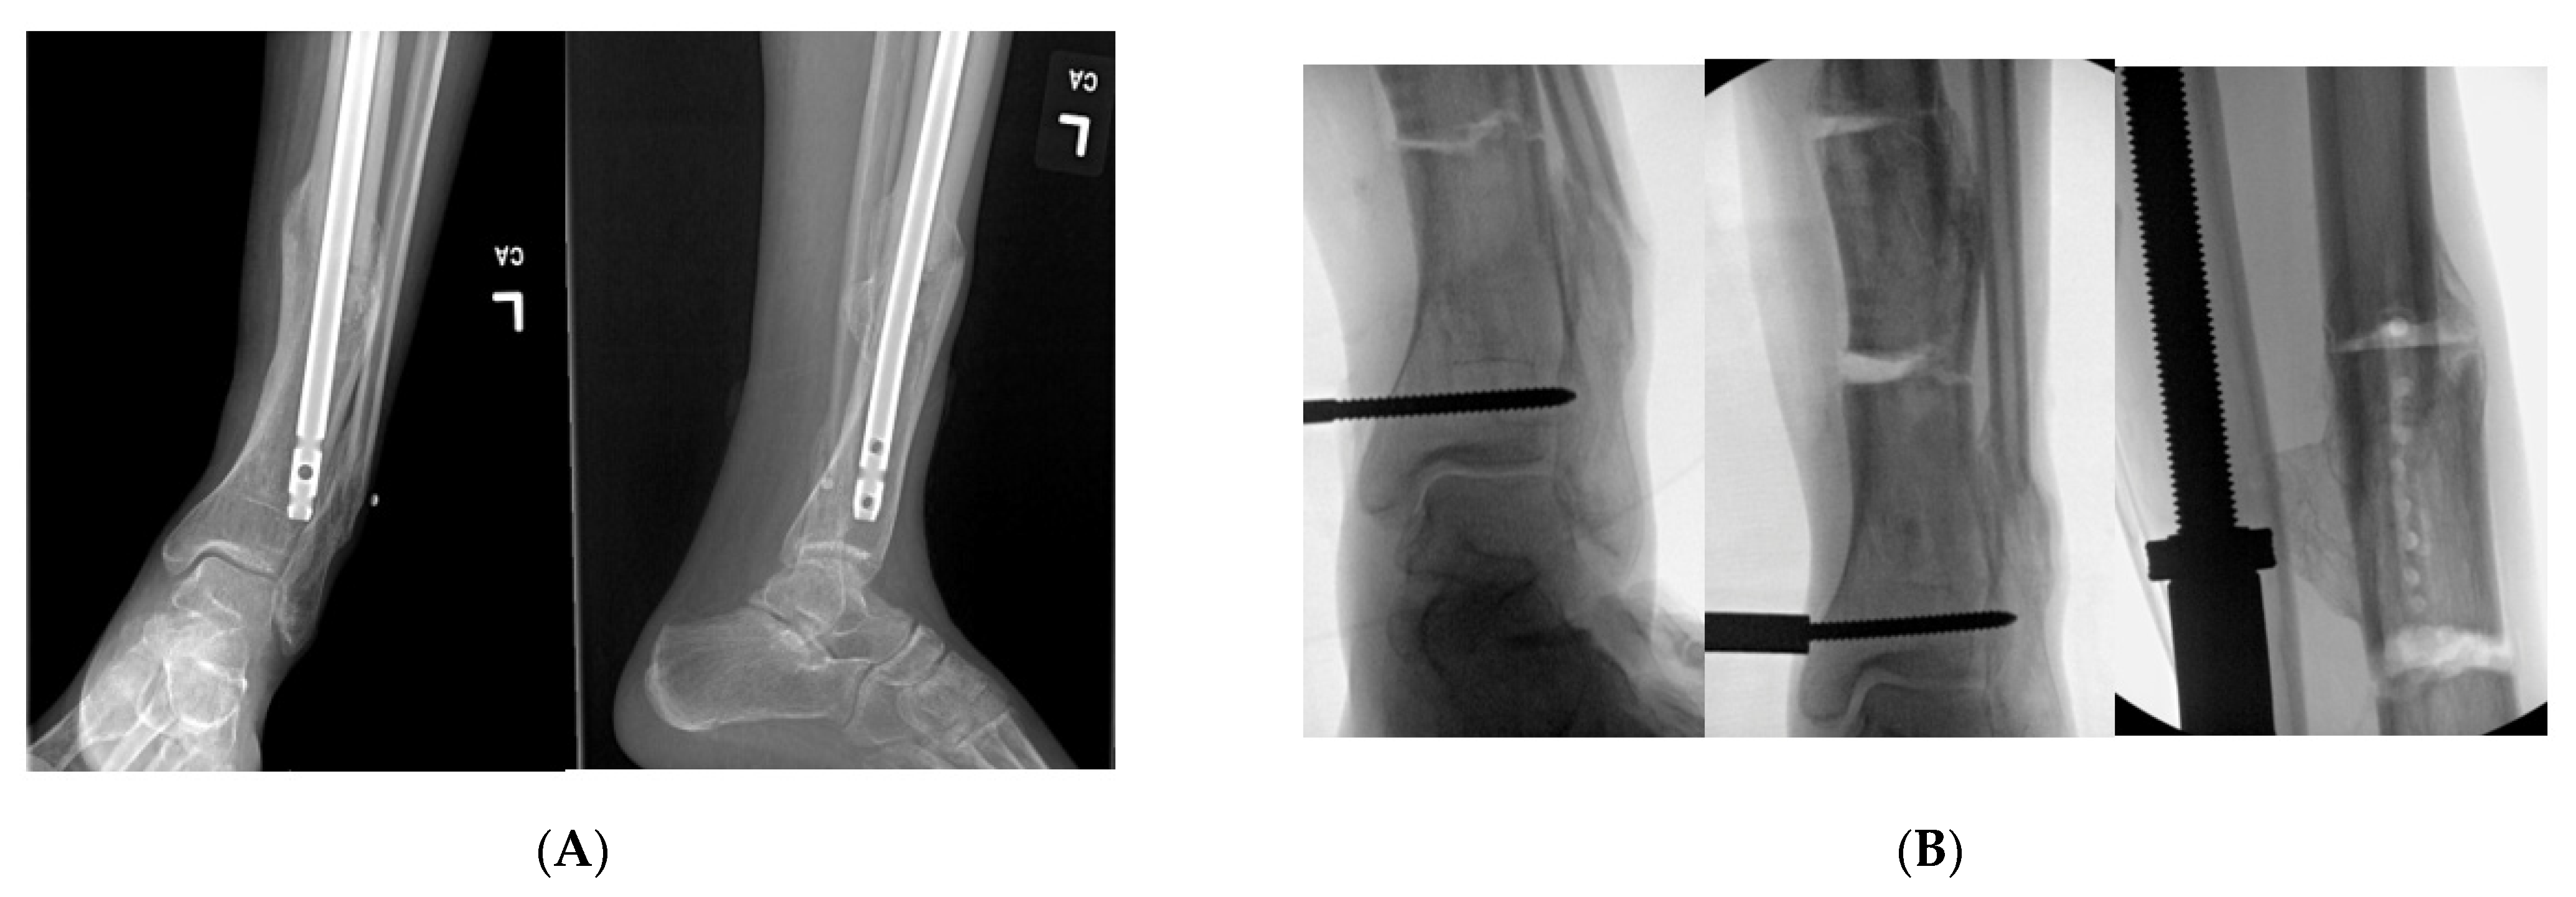

A young adult presented for orthopedic evaluation secondary to a chronic history of right knee pain. Her past medical history was significant for Russell Silver Syndrome. This is a rare genetic disorder characterized with multiple physiologic and phenotypic manifestations including short stature, scoliosis, hand abnormalities, and limb length discrepancy amongst other musculoskeletal issues (references). The physical exam was significant for bilateral genu valgum more pronounced on the right lower extremity, a limb length discrepancy with a longer right lower extremity, and excessive femoral anteversion with significant variance in hip range of motion. A full-length radiographs (Figure 5A) and computed tomography (CT) anteversion study (Figure 5B) demonstrated mild lateral mechanical axis deviation (MAD), a 2 cm LLD and 52° of femoral anteversion of the right lower extremity. Her lateral MAD was thought to be related to rotational malalignment than valgus malalignment. Magnetic resonance imaging (MRI) of the right knee ruled out any intra-articular pathology as a source of morbidity. A trial of physical therapy and non-steroidal anti-inflammatory drugs did not resolve her knee pain. She opted for surgical intervention (Figure 5C–H) to ameliorate the patellofemoral pain and LLD. Her pain subsided significantly after surgery. She went on to heal her osteotomy uneventfully.

Figure 5. (A): Full length standing radiograph. There is not a diaphyseal malunion; the patient has a 2 cm LLD, and rotational malalignment. The clamshell osteotomy was used to shorten and correct the rotational malalignment. (B): Computed tomography anteversion study demonstrating a 52° degree femoral anteversion and 30° femoral anteversion of the right and left lower extremity, respectively. (C): Intraoperative fluoro view showing bicortical drill holes being created in a diaphyseal segment measuring 2 cm. (D): An osteotome is used after the bicortical drill holes. Subsequently, a saw was used for the perpendicular cuts at the proximal and distal aspect of the osteotomy to create the clamshell. (E): Lateral fluoro view illustrating the clamshell osteotomy. No secondary fracture lines were propagated during this osteotomy. (F): 2.0 kirschner wire was placed in the proximal and distal aspect to be used as reference points when correcting the rotational malalignment. (G): AP fluoroscopic view after the clamshell segment was mobilized, and rotational malalignment was corrected. Her right knee was taken through range of motion after surgery to ensure there was not any patellofemoral maltracking. (H): AP and lateral femur XR demonstrating osseous healing of osteotomy at 6 months follow up.